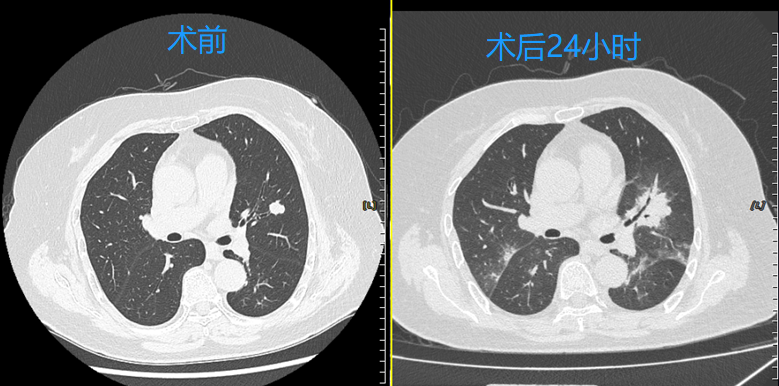

快速康复:患者术后当日即可下床活动,术后24小时复查胸部CT,冷冻消融区域覆盖结节病灶,3天后顺利出院,生活质量不受影响。